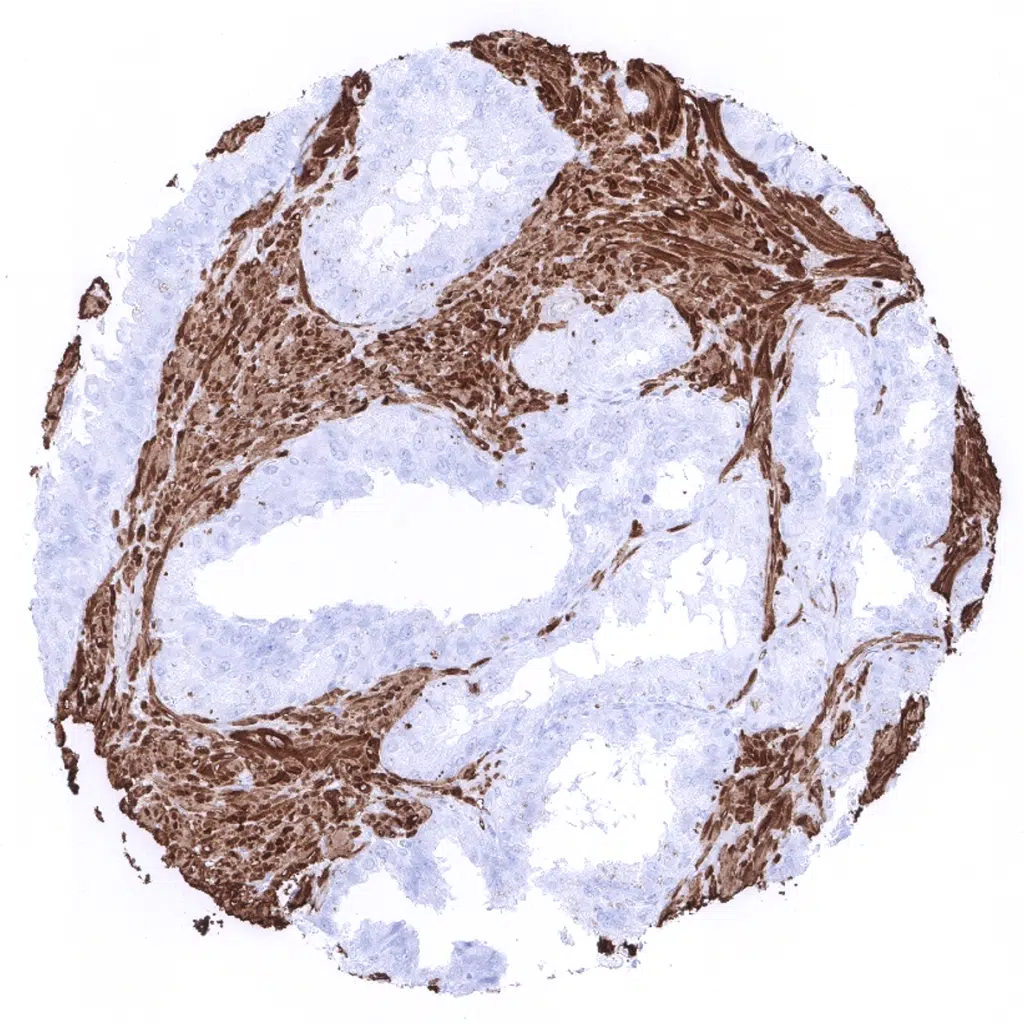

Calponin 1 antibody [MSVA-455R] HistoMAX

Tonsil